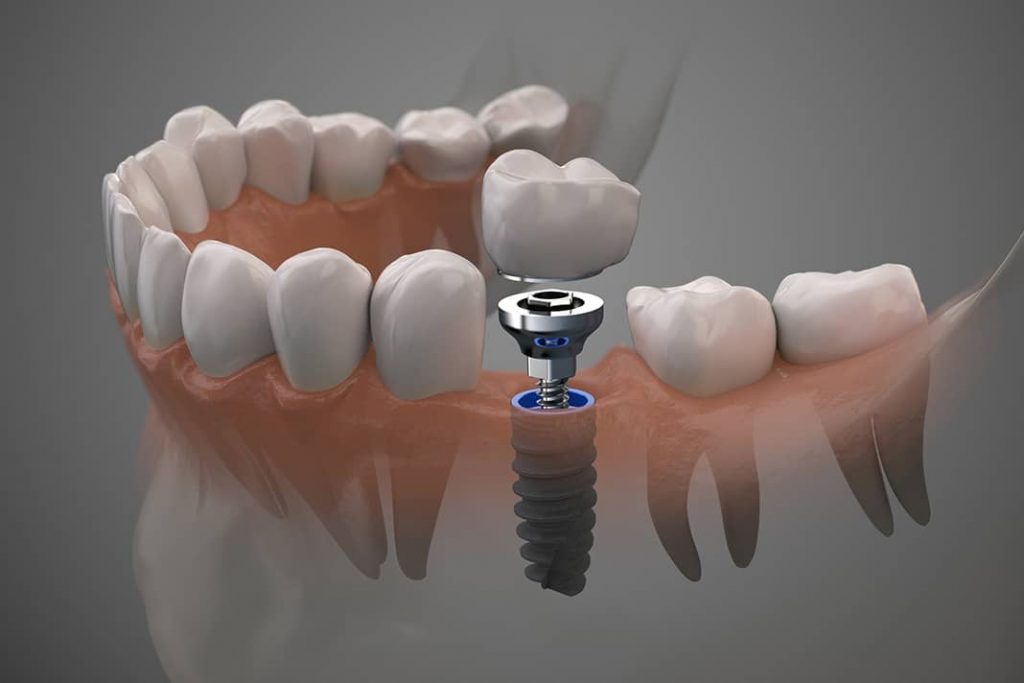

ایمپلنت دندان یک روش پیشرفته برای جایگزینی دندانهای از دست رفته است که با قرار دادن یک پایه فلزی در فک و نصب دندان مصنوعی روی آن، دندانی طبیعی و پایدار ایجاد میکند.

جراحی ایمپلنت: در این مرحله، ایمپلنت (پیچ تیتانیومی) در استخوان فک قرار داده میشود. این فرآیند تحت بیحسی موضعی انجام میشود.

قرار دادن اباتمنت: پس از پیوند کامل ایمپلنت، اباتمنت (اتصالدهنده) بر روی ایمپلنت قرار میگیرد تا روکش دندان به آن متصل شود.

روکش نهایی: در آخر، روکش دندان ساخته شده و به اباتمنت متصل میشود تا دندان جدید به طور طبیعی عمل کند و ظاهری زیبا و طبیعی داشته باشد.